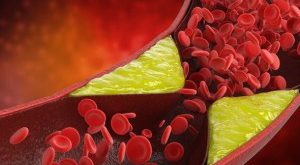

کیسه صفرا یک ارگان کوچک در زیر کبد در بالای شکم است . این قسمت مایع زرد و سبز رنگی را در خود نگه می دارد که به هضم غذا کمک می کند . بیشتر سنگ های کیسه صفرا زمانی شکل می گیرند که کلسترول زیادی در آن ها وجود داشته باشد . مصرف قرص های ضد بارداری،حاملگی،کاهش سریع وزن به دنبال یک رژیم غذایی سخت و مصرف برخی داروها می توانند سنگ کیسه صفرا را ایجاد کنند.

طبق مطالعات انجام شده ، 80 درصد از سنگ های کیسه صفرا از کلسترول ساخته شده اند . 20 درصد باقیمانده سنگ های کیسه صفرا از نمک کلسیم و بیلی روبین ساخته شده اند و هنوز علت دقیق تشکیل سنگ های کیسه صفرا مشخص نشده است اما تئوری هایی در این مورد وجود دارد .

کلسترول بیش از حد بالا در صفرا می تواند سنگ های زرد کلسترولی را بسازد که این سنگ های سفت و سخت ممکن است در صورت ساخت کلسترول توسط کبد شما افزایش پیدا کنند و نتوانند در صفرا حل شوند .